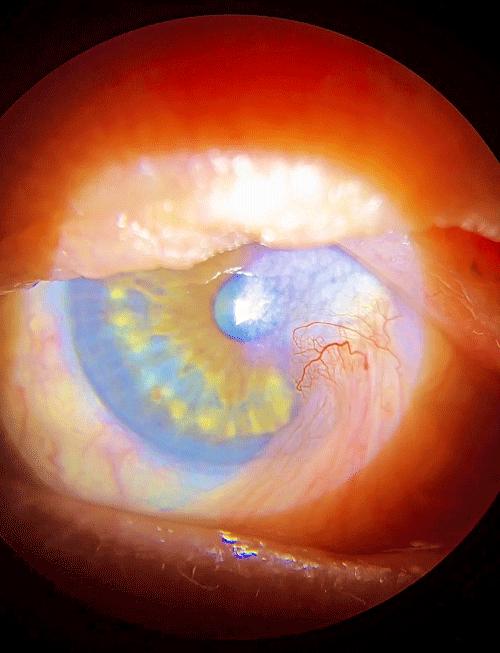

Ureteric Fibroepithelial Polyp in a Child-Recurrent Presentations and Diagnostic Dilemma Open Access

Ureteric Fibroepithelial Polyp in a Child-Recurrent Presentations and Diagnostic Dilemma

Swamy KB, Govani DR, Mehta AR, et al.

Benign ureteral polyps, also known as fibroepithelial polyps, can cause upper urinary tract obstruction by growing to block the flow of urine from the kidney. Fibroepithelial polyps are very rare benign lesions originating from the mesoderm. We have presented an interesting and unusual case who…...